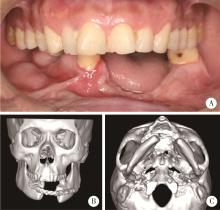

图3

病例4影像资料"

病例5影像资料"